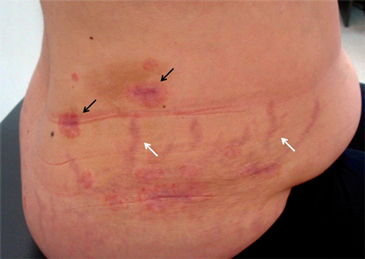

Un mes posterior a la cirugía, reaparecieron múltiples placas eritémato-descamativas en abdomen, brazos, rodillas, pies (Figura 1), y sobre las incisiones de los puertos de laparoscopía por fenómeno de Koebner (Figura 2), comprometiendo aproximadamente un 20% de la superficie corporal. En comparación a la evolución previa a la adrenalectomía, la reactivación comprometió una mayor superficie corporal y las lesiones fueron de mayor grosor.

Figura 2. Fenómenos cutáneos en flanco derecho. Se observan los cambios característicos del SC como la obesidad central y las estrías rojo-vinosas (flechas blancas). Tras 5 días de corticoides tópicos aún se observan algunas placas psoriáticas donde destacan las que aparecieron por fenómeno de Koebner sobre las incisiones de los puertos de laparoscopía (flechas negras).